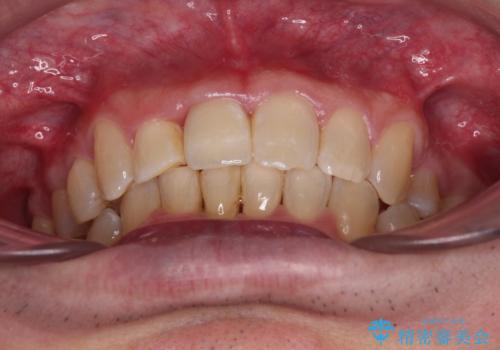

矯正治療後にはオーダーメイドタイプのオールセラミッククラウンを装着し、自然な口元に仕上がりました。